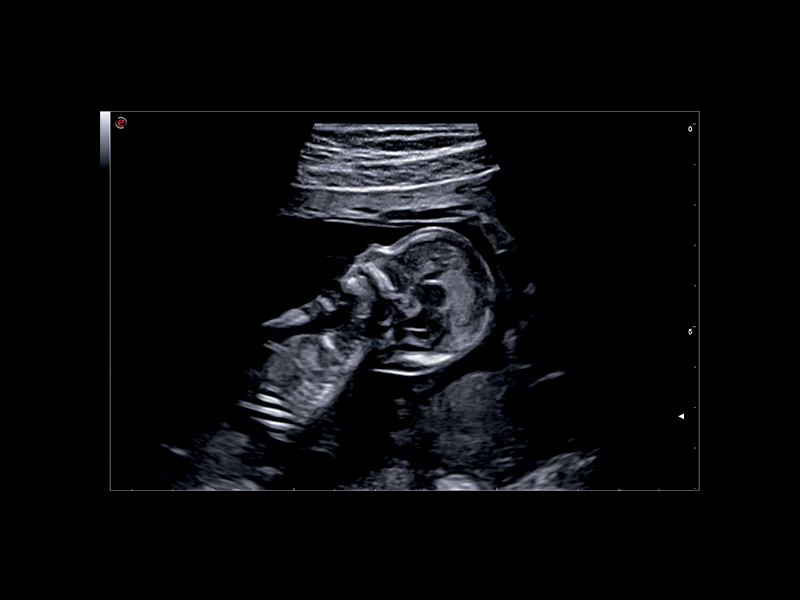

Seamless Image Quality

To ensure high-quality images from early pregnancy to birth, Esaote offers a wide range of probes, enabling end users to interrogate fetal anatomy with confidence and accuracy.

Recent technology embedded in the new C 2-9 high-frequency convex probe leverages a combination of advanced equipment, together with specifically designed transducer geometry, thus allowing the detection of the minute details of the fetus with outstanding image quality. Furthermore, the advanced image post-processing techniques help to increase clinicians’ diagnostic confidence and facilitate examination of fetal anatomy, from head to toe.

Clinical Images